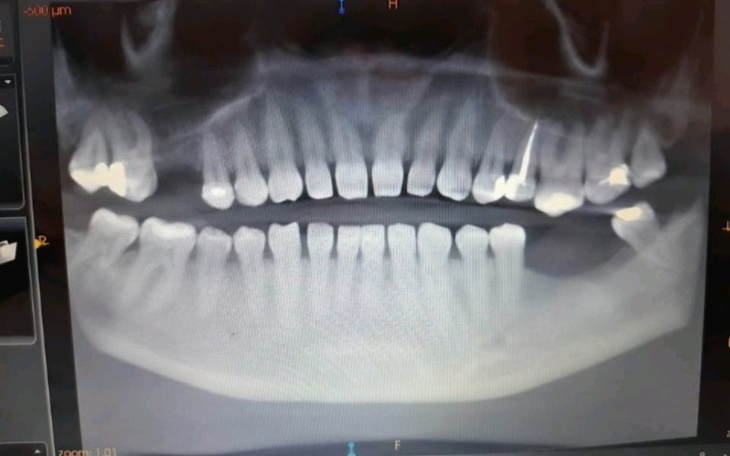

Hej jestem Olga. Mam 30 lat. 3 lata temu zaczal boleć mnie ząb, okazało się że w zębie który był zaplombowany 13 lat temu jest wiertło (stomatolog przy leczeniu nie poinformował że złamało się wiertło tylko zaplombował ząb). Ząb oczywiście chciałam ratować... długie leczenie kanałowe pod mikroskopem i próba wyciagniecia wiertła. Po długim leczeniu i wyciągnięciu wiertła zrobił się okropny stan zapalny. Pani stomatolog powiedziała że już nic nie jest w stanie zrobić. Ząb musiałam wyrwać. 2500 zł kosztowało mnie leczenie tego zęba który bankowiec musiałam wyrwać. Kolejny ząb stan zapalny okazało się że kanał nie był do końca wypełniony. Konieczność wydania kolejnego zęba. Myślałam że dam radę tak chodzić z brakiem tych zębów bo nie stać mnie na implanty. Żuchwa zaczęła boleć... po kilku latach widzę że żeby górny odsłonił szyjki i te zęby się wydlużyły w kierunku tych ubytków. Sąsiadujące zęby zaczęły się wykrzywiac też w kierunku tych pustych miejsc. Kość żuchwy w tym pustym miejscu zniknęła zrobiła się dosłownie dziura. Dziąsła sąsiadujących zębów też mają odsłonięte szyjki. I najgorsze co może w tym być asymetria twarzy przez te ubytki ponieważ mięsień policzka zanikł. To mnie najbardziej przytłacza. Wygląd 10 lat starszy... worki pod oczami opadnięty policzek i opadnięty kącik ust. Opadnięta powieka... Nie wystarcza same implanty muszę zrobić też argumentację kośći żuchwy ponieważ z 1 strony zaniknęła. Bardzo proszę o pomoc. Pomoże mi to.